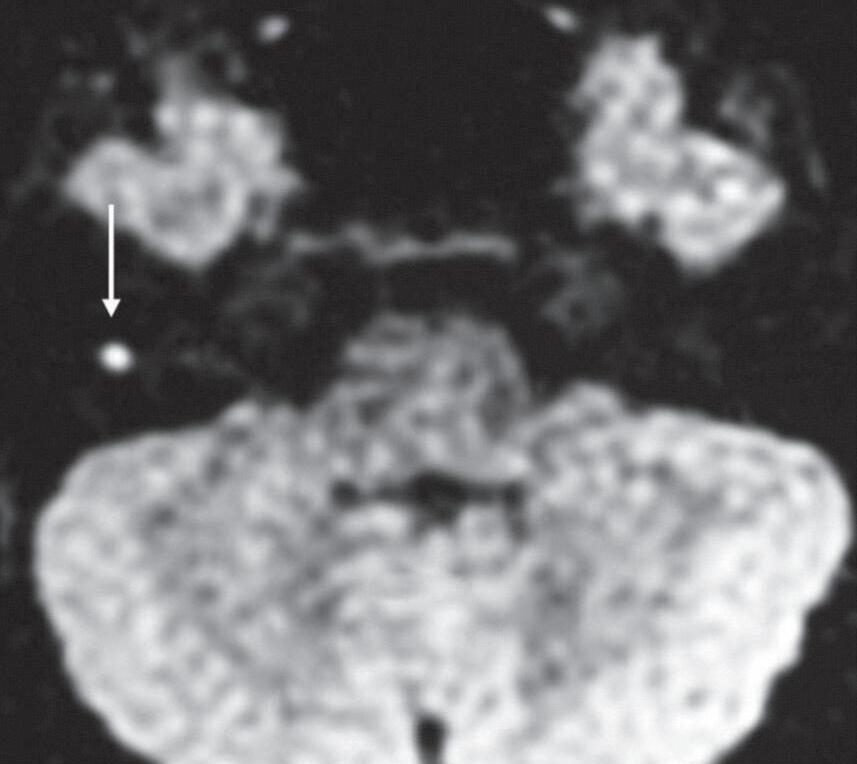

Difusão refere-se ao movimento randômico das moléculas de água no meio, conhecido como movimento browniano. O sinal hiperintenso na sequência difusão pode decorrer da restrição à difusão ou do aumento do tempo de relaxação T2 do tecido (efeito T2), questão que pode ser esclarecida com a medida do coeficiente de difusão aparente (ADC). De forma simplista, quando a lesão restringe a difusão, o ADC exibe hipossinal.

A sequência difusão pode ser utilizada na avaliação das orelhas para caracterizar colesteatomas, cistos epidermoides na cisterna do ângulo pontocerebelar, demonstrar coleções purulentas intra e extratemporais, principalmente intracranianas, investigar tumores da base do crânio intra e extra-axiais que apresentem relação núcleo/citoplasma alta (Figs. 1-19 e 1-20).

Fig. 1-20. Colesteatoma recidivado na parede posterior da cavidade timpânica. TC axial: lesão nodular hipoatenuante (seta), adjacente ao recesso do facial e seio timpânico, mastoidectomia com cavidade fechada (a). RNM sequência difusão (b): lesão focal com restrição à difusão (seta), o sinal fica hiperintenso nesta sequência.